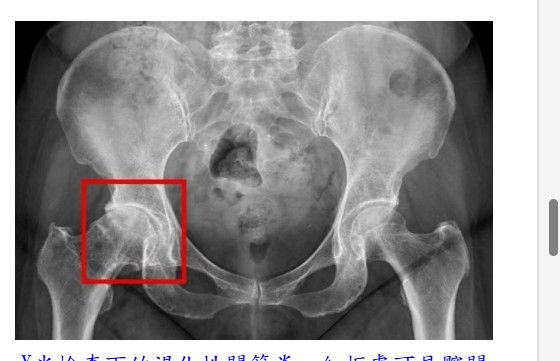

X光檢查下的退化性關節炎,紅框處可見髖關節軟骨磨損嚴重,導致骨頭間縫隙狹窄、引發發炎與疼痛。(台北慈濟醫院提供)

收治病人的台北慈濟醫院骨科醫師黃振文表示,髖關節是人體中最大的負重關節之一,由骨盆的髖臼與大腿骨頂端的股骨頭所構成,為穩定度高、活動範圍廣的球窩關節。其表面覆蓋著光滑的軟骨,可有效減少日常活動中的摩擦並吸收衝擊。一旦軟骨因老化、長期磨損或外傷受損,便可能導致骨頭間直接摩擦,引發發炎與疼痛。

黃振文醫師指出,髖關節問題初期多在活動時才引發疼痛,隨著病情加劇,在休息或夜間也無法緩解。臨床上,病人會出現鼠蹊部、大腿內側、下背部疼痛,並伴隨關節僵硬或有「喀喀」聲、使行動受限、跛行。